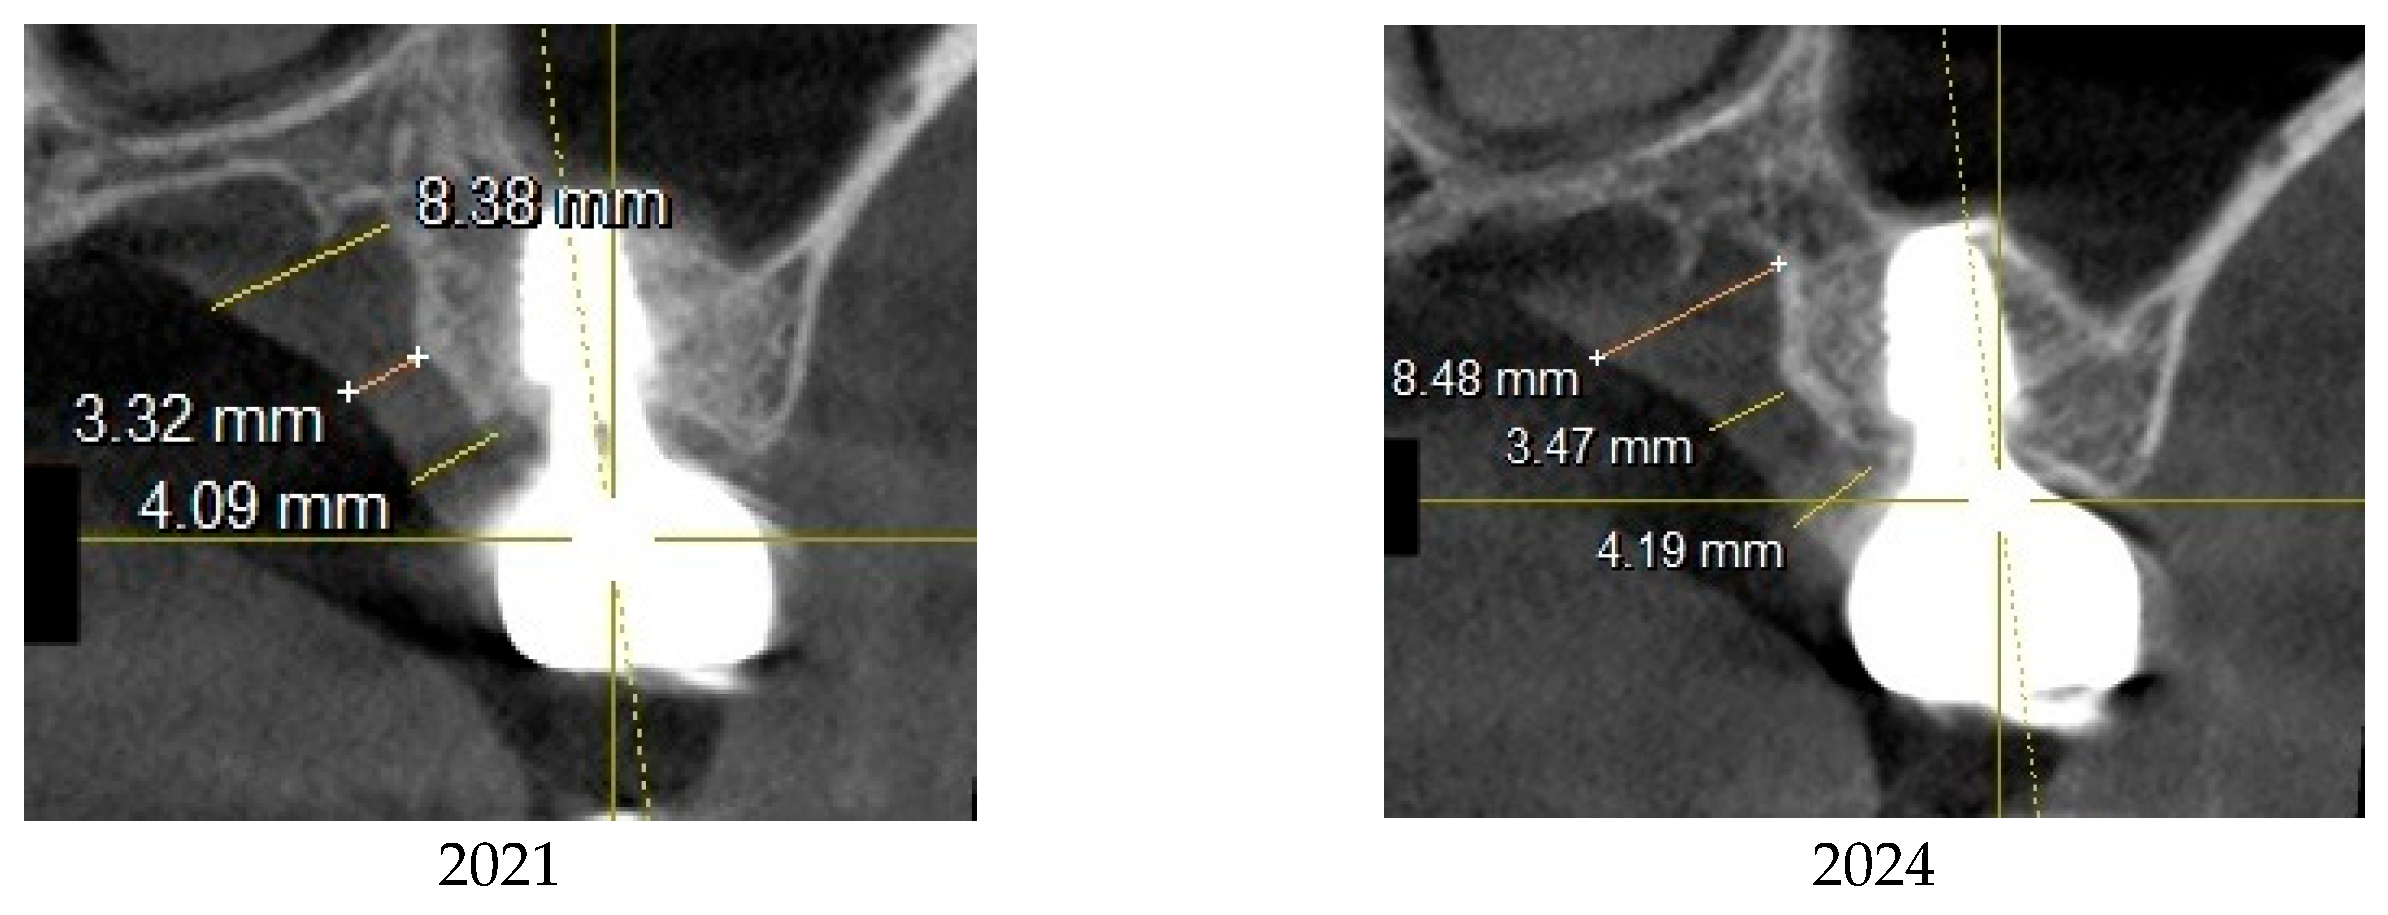

Zirconia crowns were cemented onto the prefabricated abutments (manufactured by Warrentec) using the extraoral cementation technique. (Figure 4)

The analysis suggested that the increased CRD in the upper left first molar implant may have contributed to the development of peri-implant mucositis. To address this, it was decided to remake the restoration for the upper left implant, aiming to adjust the CRD to the optimal range as indicated by the data. A new restoration was fabricated using a 4.5 mm diameter, 3 mm gingival cuff abutment, and subsequently delivered to the patient (Figure 5).

Following the restoration remake, the patient reported no further discomfort related to the implant, including gingival bleeding, swelling, or food impaction. Clinical examinations confirmed healthy peri-implant soft tissue, with no signs of radiographic bone resorption. The sulcus was probed using the Implant Paper Point Probe (IPPP), a device specifically designed for probing the peri-implant sulcus and applied with a yield strength of 0.35 N (manufactured by Sure Endo, Seoul, South Korea). The probing depth consistently measured less than 1 mm, with no evidence of bleeding. These findings confirm the successful resolution of peri-implant mucositis.

Figure 6 illustrates the comparison between the two restorations before and after the revision, highlighting differences in their profiles. It also includes a panoramic X-ray taken after the revision procedure and clinical photographs captured on October 31, 2022 following the restoration adjustment. (Figure 6)

Figure 7 and Figure 8 illustrate the radiographic changes observed from 2021 to 2024 at the lower right first molar implant site (control site) and the upper left first molar implant site (experimental site), respectively. (Figure 7, Figure 8) The clinical photographs taken in 2024 (Figure 9) depict the final results, showcasing both a stable and natural appearance for both implant sites.

This figure presents clinical photographs of the control and experimental implant sites following the revision procedure. Both sites exhibit a natural and healthy appearance, indicating successful soft tissue adaptation and restoration aesthetics, taken at 2024.

Figure 6. The upper left image presents a comparison of the two restorations before and after the revision, while the upper right image shows a panoramic X-ray taken post-revision. The lower two images display the clinical appearance of the upper left first molar implant restoration following the revision procedure conducted on October 31, 2022.

Preprints 151394 g006

Figure 9. Clinical images of control and experimental sites post-revision.

Preprints 151394 g009